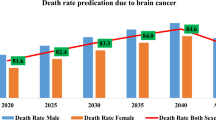

Predictive models in radiology can now be constructed with remarkable accuracy using an amalgamation of radiomics and artificial intelligence. To effectively prepare for surgical procedures and assess the progression of the tumor, accurate segmentation of gliomas is essential. The current study aims to address a segmentation of the whole tumor (WT), tumor core (TC), and enhancing tumor (ET), three partially overlap** regions of interest within the glioma with two variants, high-graded glioma (HGG) and low-graded glioma (LGG), made available through the BraTS 2019, 2020, and 2021 challenges. The traditional approach has been bypassed by focusing only on the network architecture, but rather the proposed research work is also concentrating on data pre-processing, augmentation, training, and testing strategies to improve the performance of the automatic brain tumor segmentation. UNet and its variants have recently been shown to be effective in automatically segmenting brain tumors from volumetric multi-modal magnetic resonance (MR) images. Motivated from the literature, an improved UNet + + framework (ResUNet + +) is proposed to segment multi-modal volumetric MR images of brain tumor. The ResUNet + + is a 3D (three-dimensional) encoder-decoder model where the encoder path is replaced with the pre-trained backbone of the ResNet50 model. Moreover, the standard convolutional blocks of the traditional UNet architecture are substituted with the 3D dense convolutional blocks, and in the decoder phase, convolutional layers are replaced by the convolutional transpose layers (ConvTranspose), outperforming the existing models in terms of segmenting the WT, TC, and ET in both HGG and LGG. The performance of the ResUNet + + framework is evaluated using five different performance parameters, and when compared with the state-of-the-art models, the results demonstrate the effectiveness of the framework.

Ostrom QT, Gittleman HR, Xu JC, Kromer C, Wolinsky Y, Kruchko C, Barnholtz-Sloan JS (2016) CBTRUS statistical report: primary brain and other central nervous system tumors diagnosed in the United States in 2009–2013. Neuro Oncol 18(suppl_5):v1–v75